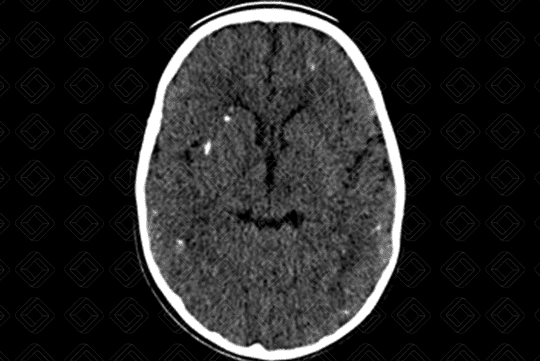

• Achados de imagem neurológicos: O rastreio inicia-se com ultrassonografia transfontanelar. Diante da gravidade das lesões e para avaliar a extensão das calcificações, pode ser realizada adicionalmente, tomografia computadorizada do crânio e até mesmo, ressonância magnética . Calcificações puntiformes periventriculares (subependimárias) são características, microcefalia (depende do momento da infecção fetal - as que ocorrem no período gestacional mais precoce são mais graves), distúrbios de migração neuronal e hipoplasia cerebelar.